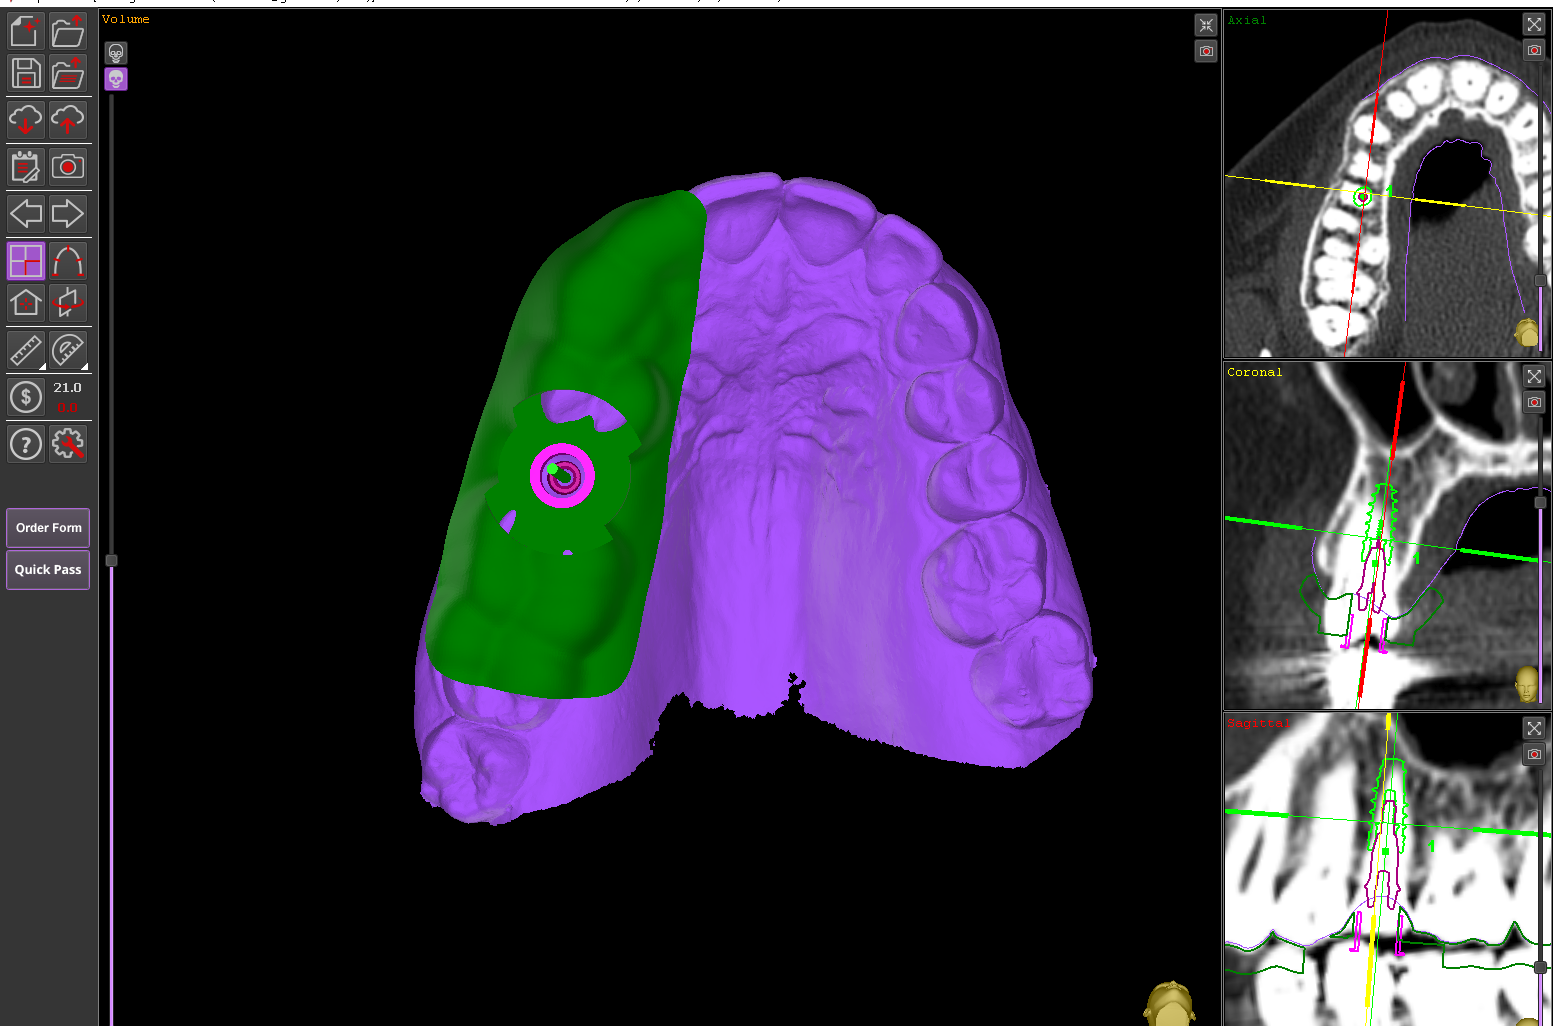

Ubicación precisa del implante

Colocar implantes completamente rodeados de hueso asegura su durabilidad y estabilidad

Cirugía Guiada por Ordenador

En nuestra clínica, ofrecemos cirugía guiada utilizando software 3D exacto, una técnica innovadora que nos permite planificar con precisión la colocación de los implantes y asegurar su correcta integración en el hueso maxilar o mandibular. De esta manera, podemos garantizar una colocación precisa, sin errores y con un mínimo de molestias para el paciente.

Durante la cirugía, se utilizan guías quirúrgicas personalizadas basadas en esta planificación digital. Estas guías ayudan a posicionar el implante en el lugar exacto determinado en la planificación, asegurando que esté perfectamente alineado y rodeado de suficiente hueso, lo cual es crucial para su integración y estabilidad a largo plazo. Además, esta precisión garantiza que el implante esté en la posición óptima para recibir la prótesis dental, lo que mejora la funcionalidad y estética del resultado final.